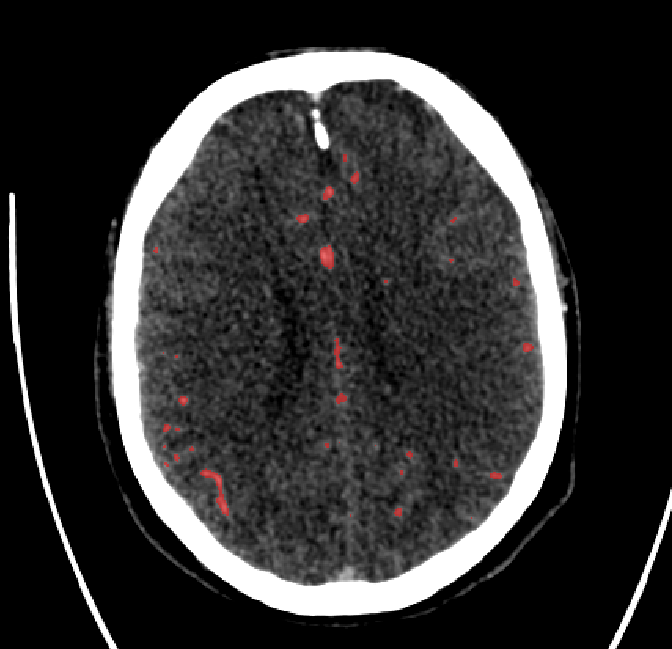

Refer to caption

(a) Axial (top-down) view.

(b) Coronal (back-front) view.

(c) Sagittal (left-right) view.

Figure 3.3: Generated vessel structures with spatial target growth incentive. The target volume was a vessel density atlas created by averaging the ground truth of patients in our data set.

Another use of the vessel atlas is to determine if a node is out of bounds. This is done by checking if the atlas has a value of 0 at the node’s position. If a leaf node is too far out of the brain, the branch is discontinued (the leaf will never be selected to spawn a child). On top of this, in order to make the overall structure more realistic, a different atlas was used for each of the two hemisphere root nodes. Such atlas would only have non-zero values for one brain hemisphere. This causes the resulting vessel structures to no longer cross over between hemispheres. A resulting example structure can be seen in Figure 3.3.